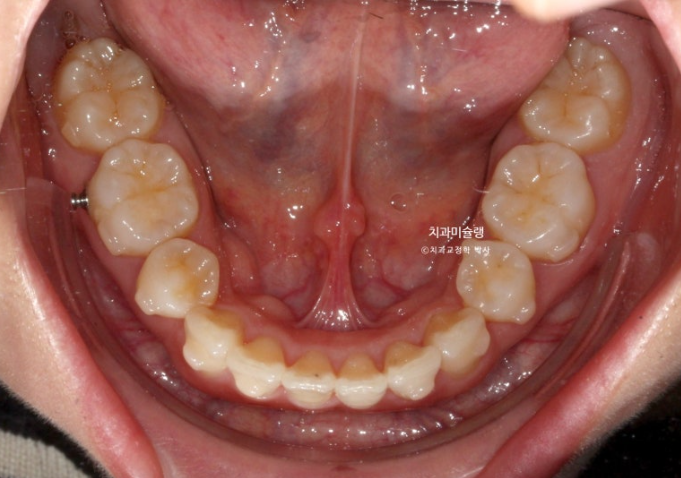

돌출입 교정을 위해 멀리 지방에서 오신 환자분입니다.

윗니 돌출이 심합니다.

아랫니 기준으로 약 1센치가 더 튀어나와 있습니다.

아래 치열은 덧니가 심한 상황입니다.

입이 안 다물어질 정도의 윗니 돌출과 심한 아래 덧니를 해결하려면 작은어금니 4개 발치는 불가피합니다.